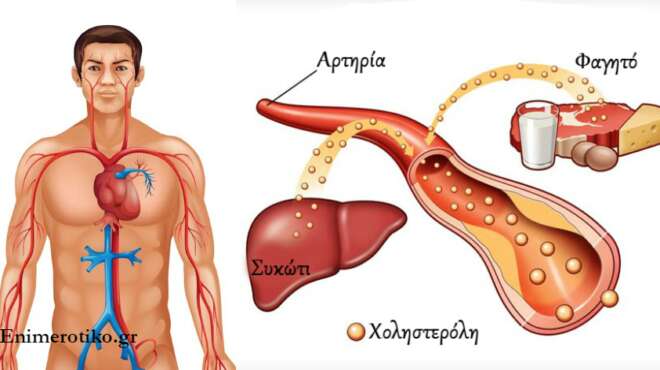

Χαμηλά επίπεδα σακχάρου

Φυσιολογικό θεωρείται το σάκχαρο που δεν ξεπερνά τα 100 mg/dL – μετράμε όταν δεν έχουμε φάει για 8 τουλάχιστον ώρες, γι’ αυτό και η μέτρηση ονομάζεται γλυκόζη ή σάκχαρο νηστείας. Αν όμως πέσει κάτω από 70 mg/dL, είτε λόγω διαβήτη είτε λόγω έντονης άσκησης, μπορεί να έχετε υπερβολική εφίδρωση και να αισθάνεστε το δέρμα σας κρύο και υγρό, ειδικά στον αυχένα και στα μαλλιά. Επαναφέρετε τα επίπεδα σακχάρου πίνοντας ή τρώγοντας κάτι γλυκό. Εάν το σάκχαρό σας συνεχίζει να πέφτει μπορεί να εκδηλωθούν και άλλα συμπτώματα που χρήζουν επείγουσας αντιμετώπισης.

Λάθος διατροφή

Το «σύνδρομο οσμής ψαριού» ή τριμεθυλαμινουρία (trimethylaminuria) είναι μια σπάνια γενετική πάθηση που κάνει τους πάσχοντες να έχουν μυρωδιά σκουπιδιών! Η μυρωδιά παραπέμπει σε ψάρι, ακαθαρσίες και οτιδήποτε μπορεί να υπάρχει στα σκουπίδια και απεκκρίνεται μέσω των πόρων του δέρματος, του ιδρώτα, των ούρων, του σάλιου, ακόμα και των κολπικών υγρών. Η πάθηση οφείλεται στο ότι το σώμα δεν μπορεί να διασπάσει τη χημική ένωση τριμεθυλαμίνη, η οποία παράγεται κατά την πέψη τροφίμων όπως τα αυγά, τα όσπρια και τα ψάρια.

Αντ ‘αυτού, αποβάλλει την ουσία μέσω του ιδρώτα, των ούρων και της αναπνοής. Οι πάσχοντες πρέπει να αποφεύγουν την κατανάλωση αυτών των τροφών και να λαμβάνουν συγκεκριμένα συμπληρώματα.

Άλλες παθήσεις

Η υπερβολική παραγωγή ιδρώτα μπορεί να οφείλεται σε μια σειρά παθήσεων, συμπεριλαμβανομένης της ουρικής αρθρίτιδας, του υπερθυρεοειδισμού και της νόσου του Πάρκινσον. Μπορεί επίσης να οφείλεται σε λέμφωμα. Πρόκειται είτε για ανοσολογική απόκριση του οργανισμού, στην καταπολέμηση του καρκίνου, είτε για αντίδραση σε υψηλό πυρετό. Ο ιδρώτας φαίνεται πως έχει σχέση τόσο με το λέμφωμα Hodgkin, όσο και με το λέμφωμα non-Hodgkin.